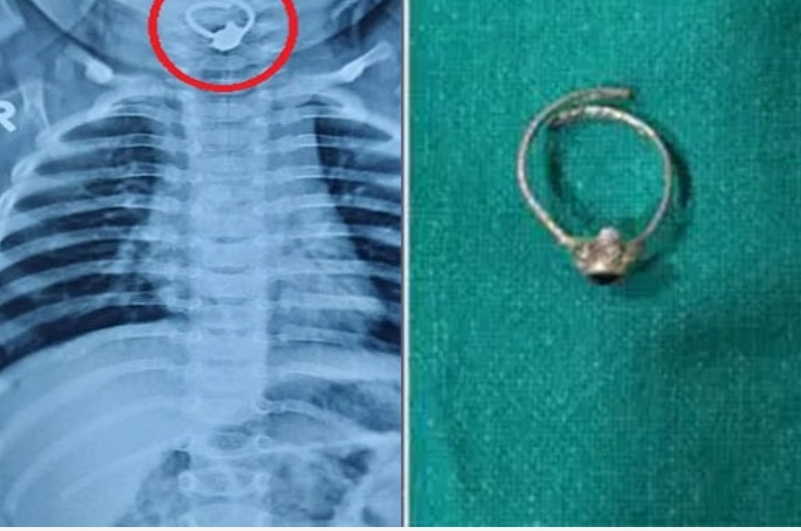

ಮಗುವಿನ ಶ್ವಾಸಕೋಶದಲ್ಲಿ ತಾಯಿಯ ಕಾಲುಂಗುರ ಪತ್ತೆ

ಮಹಾರಾಷ್ಟ್ರ: ಎಂಟು ತಿಂಗಳ ಮಗುವೊಂದು ತಾಯಿಯ ಕಾಲುಂಗುರ ನುಂಗಿದ ಪರಿಣಾಮ ಅದು ಶ್ವಾಸಕೋಶದಲ್ಲಿ ಸಿಲುಕಿಕೊಂಡ ಘಟನೆ ಬಾರಾಮತಿಯಲ್ಲಿ ನಡೆದಿದೆ. ಸದ್ಯ ಶಸ್ತ್ರಚಿಕಿತ್ಸೆ ಮೂಲಕ ಕಾಲುಂಗುರವನ್ನು ಹೊರ ತೆಗೆಯಲಾಗಿದ್ದು, ಮಗು ಪ್ರಾಣಾಪಾಯದಿಂದ ಪಾರಾಗಿದೆ.

ಕೂಡಲೇ ಇನ್ನೊಂದು ವೈದ್ಯರ ಬಳಿ ತೆರಳಿ ಎಕ್ಸ್ರೇ ಮಾಡಿಸಿದಾಗ ಶ್ವಾಸಕೋಶದಲ್ಲಿ ಗೋಲಾಕಾರದ ವಸ್ತುವೊಂದು ಸಿಲುಕಿಕೊಂಡಿರುವುದು ಗೊತ್ತಾಗಿದೆ. ಕೂಡಲೇ ಶಸ್ತ್ರಚಿಕಿತ್ಸೆ ನಡೆಸಿ ಶ್ವಾಸನಾಳದಿಂದ ಆ ವಸ್ತುವನ್ನು ಹೊರ ತೆಗೆದಿದ್ದಾರೆ.

ಅದು ತಾಯಿಯ ಕಾಲುಂಗುರವಾಗಿತ್ತು. ಸದ್ಯ ಬಾಲಕ ಚೇತರಿಸಿಕೊಳ್ಳುತ್ತಿದ್ದು, ಪ್ರಾಣಾಪಾಯದಿಂದ ಪಾರಾಗಿದ್ದಾನೆ. ದಿನಗಳೆದಿದ್ದರೆ ಬಾಲಕನ ಪ್ರಾಣಕ್ಕೇ ಕುತ್ತು ಉಂಟಾಗುತ್ತಿತ್ತು ಎಂದು ವೈದ್ಯರು ತಿಳಿಸಿದ್ದಾರೆ.